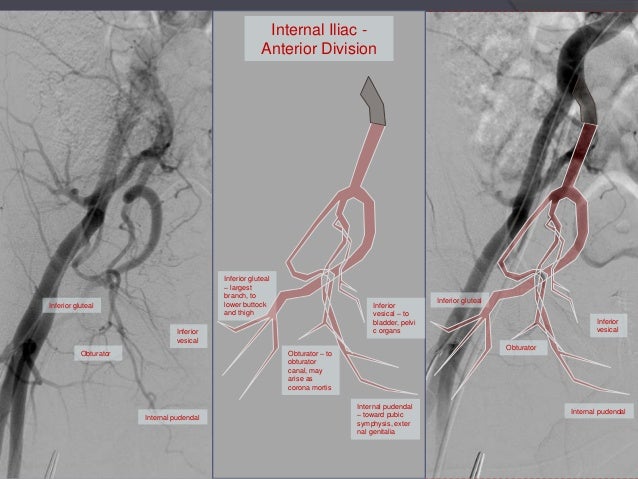

Variations Of Anterior And Posterior Division Of Internal Iliac Artery A Systematic Review And Clinical Implications Biomedical Research And Therapy